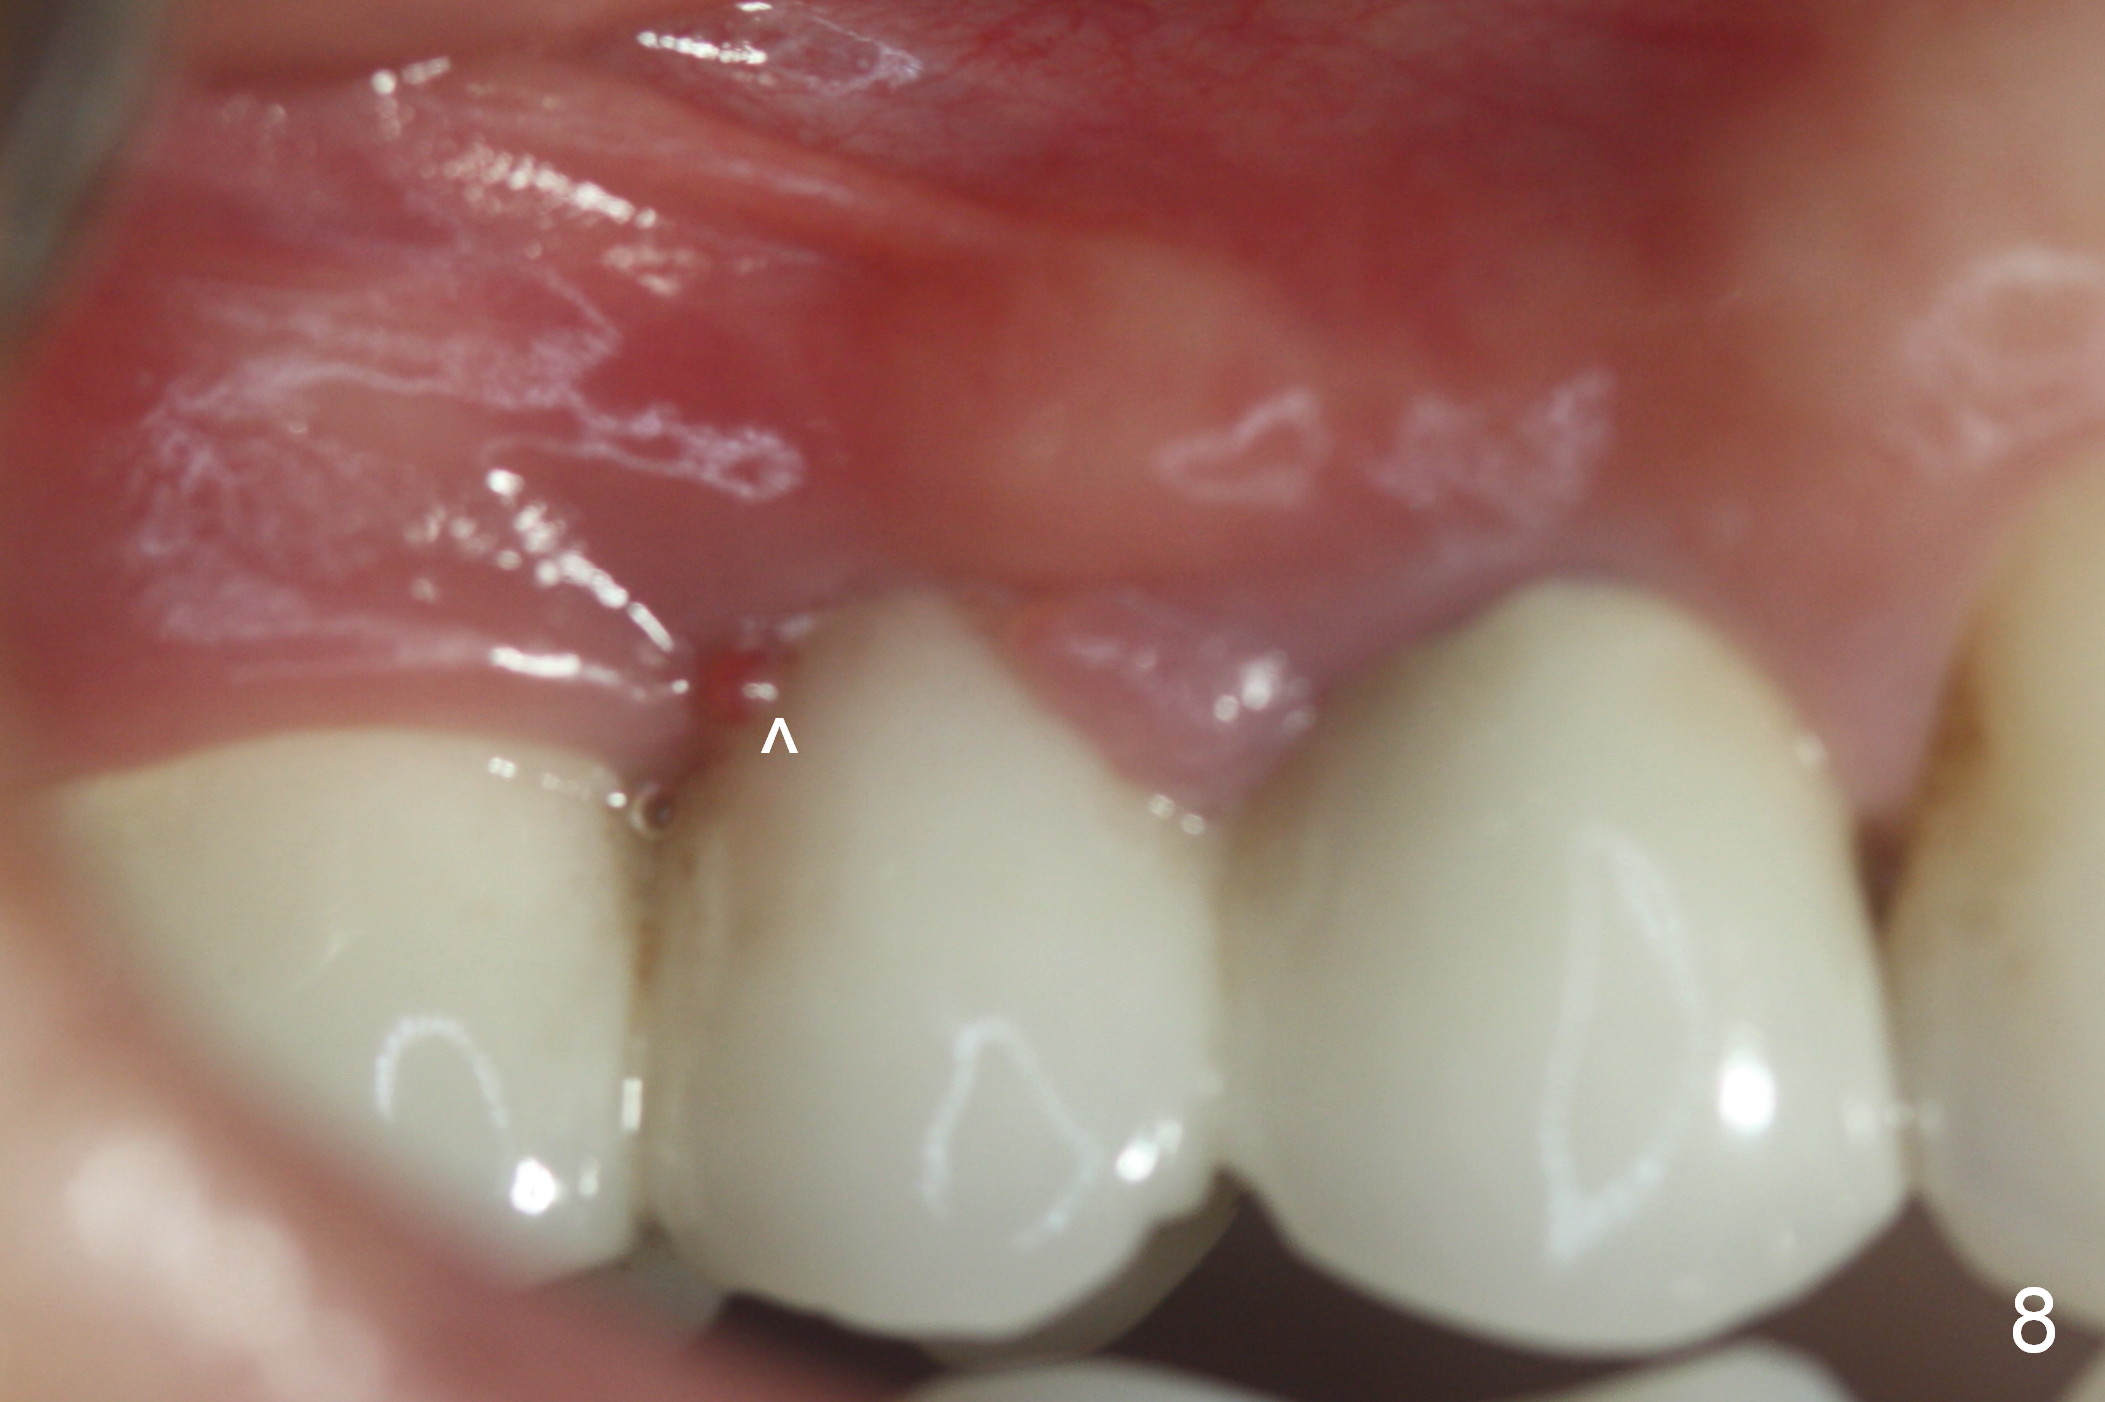

Eleven days later when the patient returns for bridge sectioning and implant placement, the pontic infection extends distally (Fig.8 <). When the bridge is sectioned, the pontic mucosa appears unsuitable for implant surgery (Fig.9). The patient is discharged after fabrication of a provisional at #5. She is rescheduled for implant placement 17 days later. IBS implant is to be placed because of its dual system. If the bone is soft, go to the bone expansion route. Otherwise, choose the traditional method: drilling.